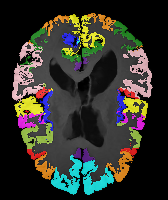

Image Manual Seg DA-1 Mono-21 DA-21 Mono-65 Refer to caption Refer to caption Refer to caption Refer to caption Refer to caption Refer to caption

Figure 2:  Examples of knee MRI registration (top) and brain MRI segmentation (bottom) results. Top: The first two columns are the moving image/segmentation and the target image/segmentation followed by the warped moving images (with deformation grids)/segmentations by different models. Bottom left to right: original image, manual segmentation, and predictions of various models. Mono-i𝑖i and DA-i𝑖i represent the mono- and DA models with i𝑖i manual segmentations respectively.

Image Manual Seg DA-1 Mono-5 DA-5 Mono-200 Refer to caption Refer to caption Refer to caption Refer to caption Refer to caption Refer to caption

Figure 4: Examples of brain MRI registration (top) and knee MRI segmentation (bottom) results. Top: The first two columns are the moving image/segmentation and the target image/segmentation followed by the warped moving images/segmentations by different models. Bottom left to right: original image, manual segmentation, and predictions of various models. Mono-i𝑖i and DA-i𝑖i represent the mono- and DA models trained with i𝑖i manual segmentations respectively.